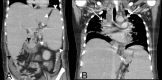

We report a 27-year-old previously healthy man, who presented with fever and painful swelling of both ankles for 6 months, and who had been jaundiced for 1 week. Clinical examination revealed diffuse macular rash, severe pallor, deep icterus, generalised lymphadenopathy and hepatosplenomegaly. Detailed evaluation revealed granulomata in bone marrow aspirate, and numerous acid fast bacilli in lymph node biopsy. Bone marrow PCR was also positive for Mycobacterium tuberculosis. A diagnosis of disseminated tuberculosis was made and antitubercular therapy was initiated. Investigation also showed features of haemophagocytosis within the bone marrow. Results of further tests satisfied the criteria for haemophagocytic lymphohistiocytosis, probably secondary to tuberculosis. However, rapid deterioration in his clinical condition led to his death within 5 days of diagnosis, before appropriate therapy for haemophagocytic lymphohistiocytosis could be instituted. This case report highlights an unusual and deadly presentation of tuberculosis in an immunocompetent individual.